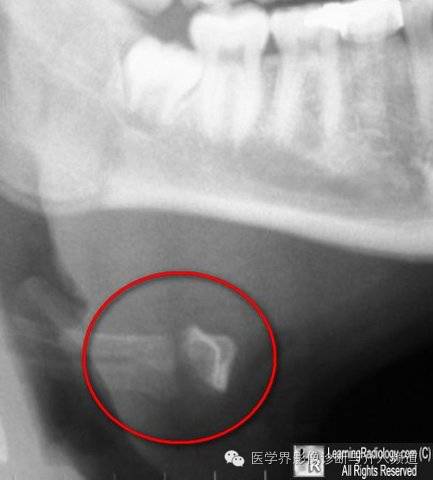

11、皮肤裂伤:皮肤裂口内空气的投影形似骨折,容易误诊。